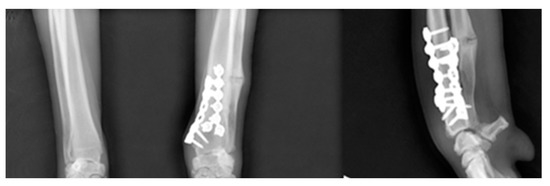

| JOA | Pre-OP | Post-OP | Target | Mean | Reference |

|---|---|---|---|---|---|

| Values | Values | ||||

| aLDRA | 57 | 85 | 85 | 86 | 85~87 |

| aCdPRA | 92 | 87 | 87 | 85 | 84~86 |

| aMPRA | 75 | 84 | 84 | 83 | 82~83 |

| aCdDRA | 62 | 77 | 77 | 77 | 76~78 |

| θ | 38 | 21 | 21 | 27 | 21~32 |